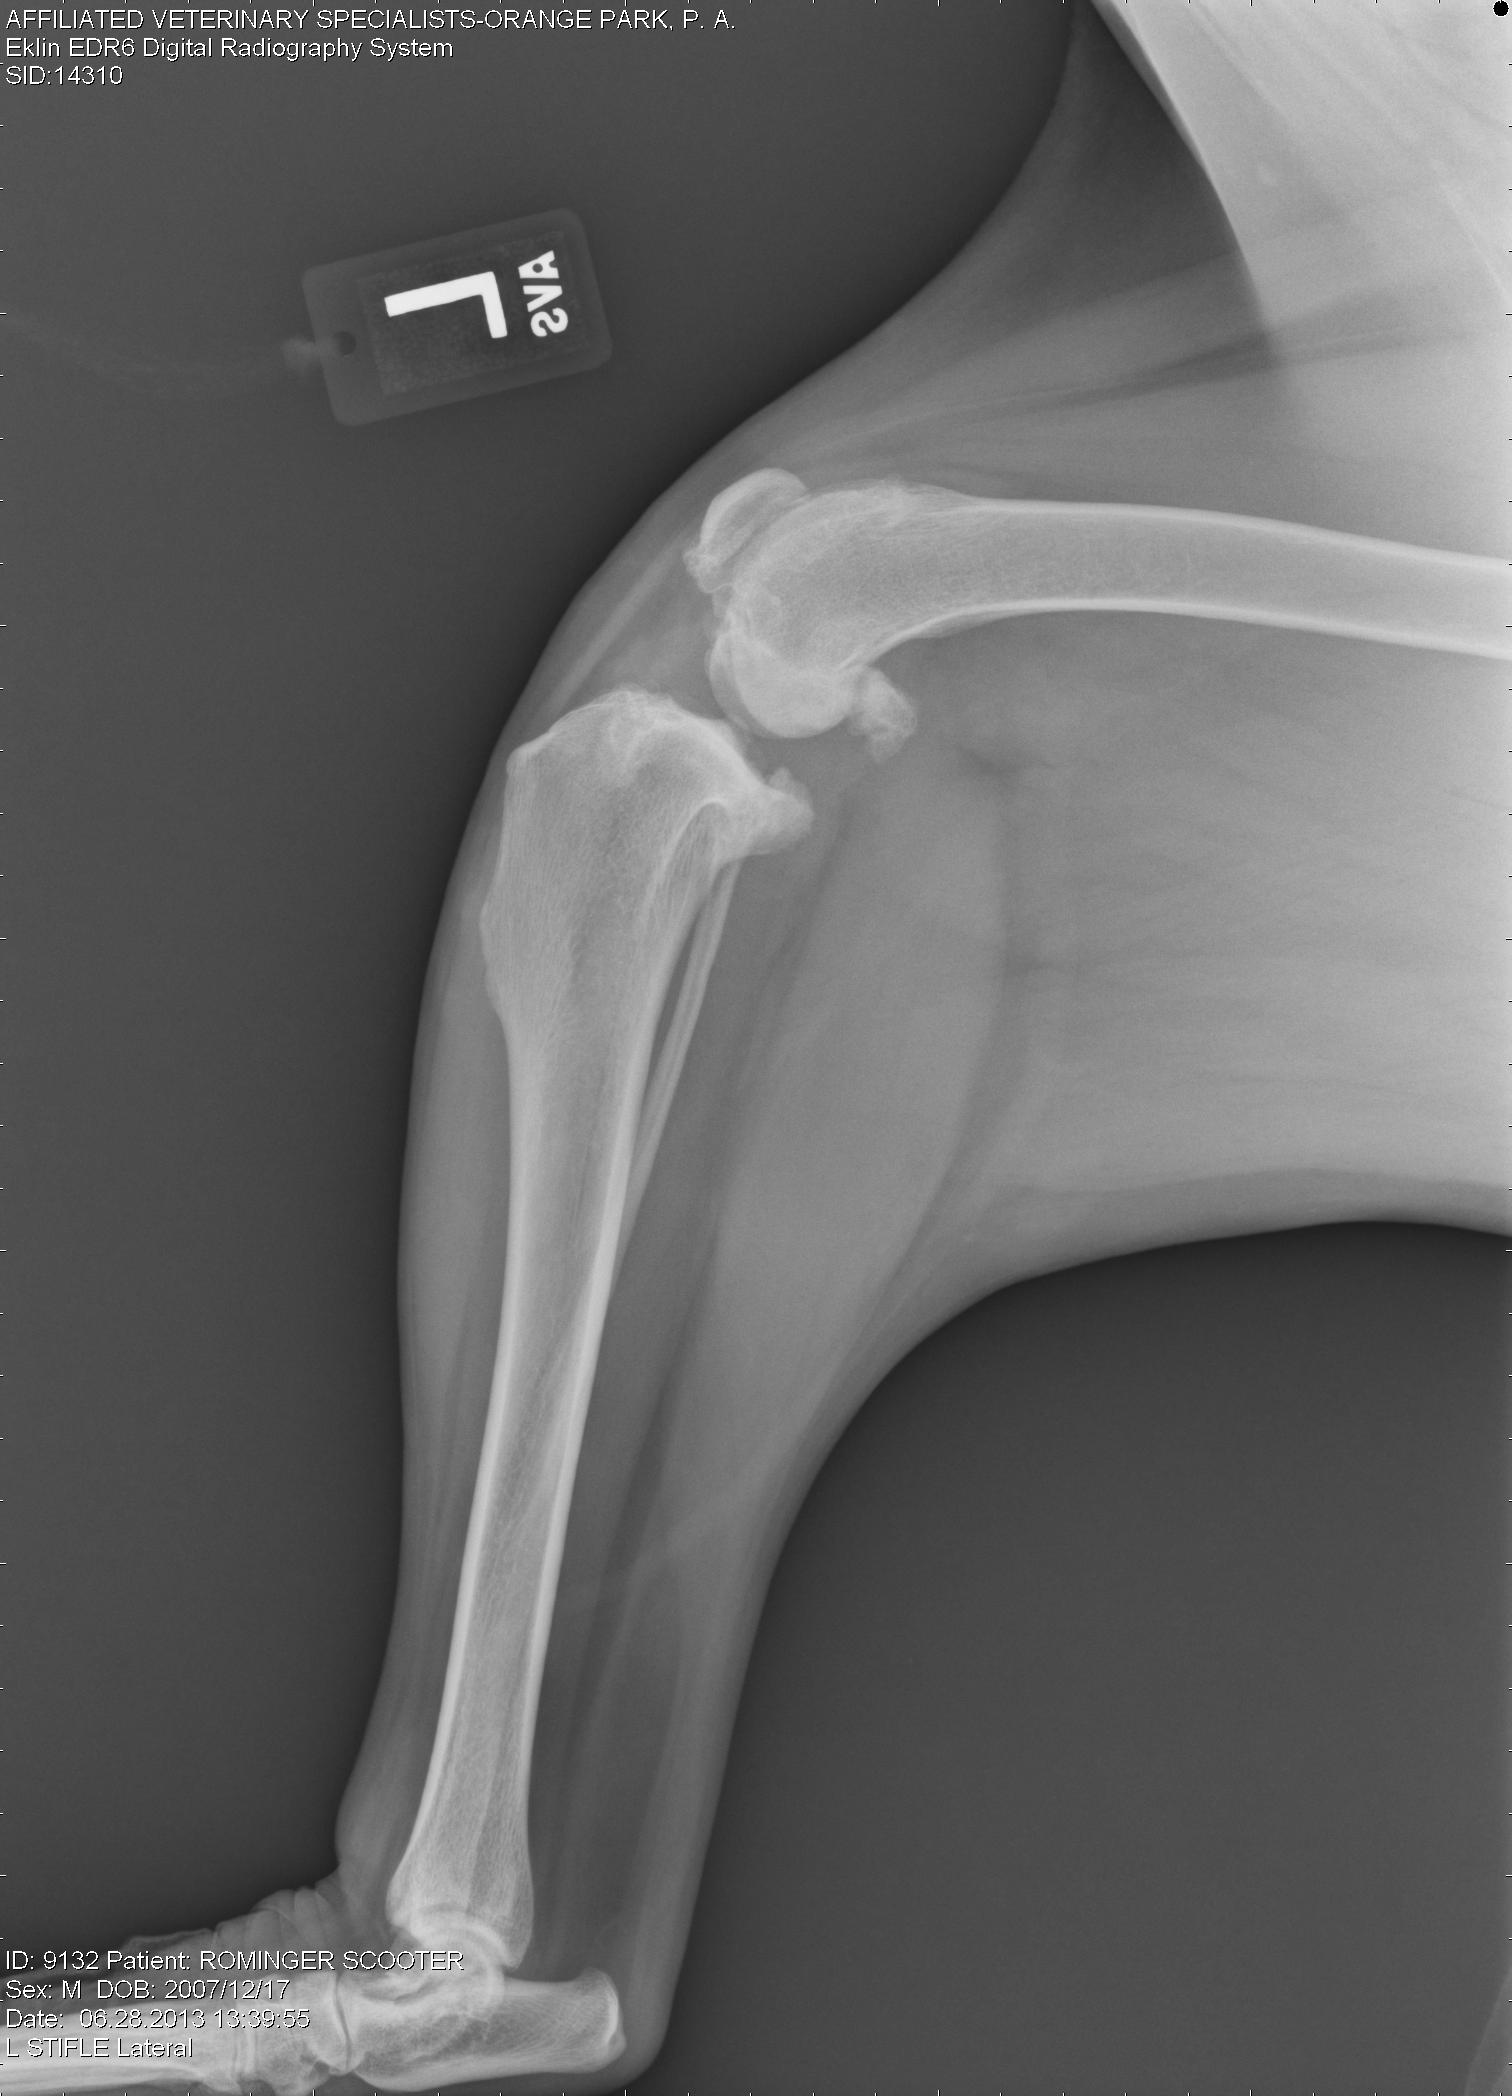

Left knee – note the joint swelling, arthritic changes, and forward movement of the tibia in relation to the femur.